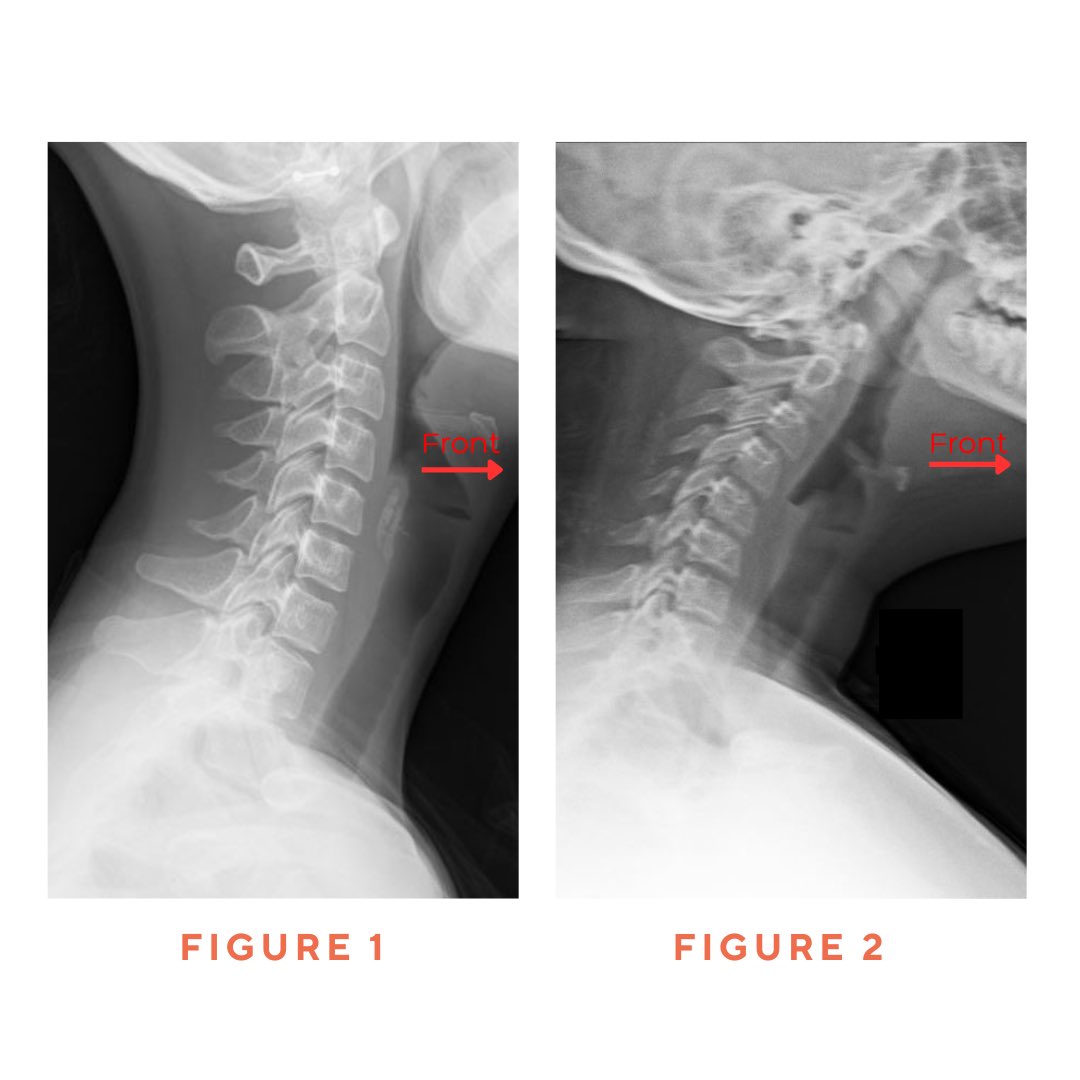

Your phone is training your posture more than you realize. The problem? It’s training you to slouch, hunch, and strain your neck. This is Text Neck, and it’s becoming a serious problem.

Your posture affects more than you think! Check out these five surprising health effects of poor posture.